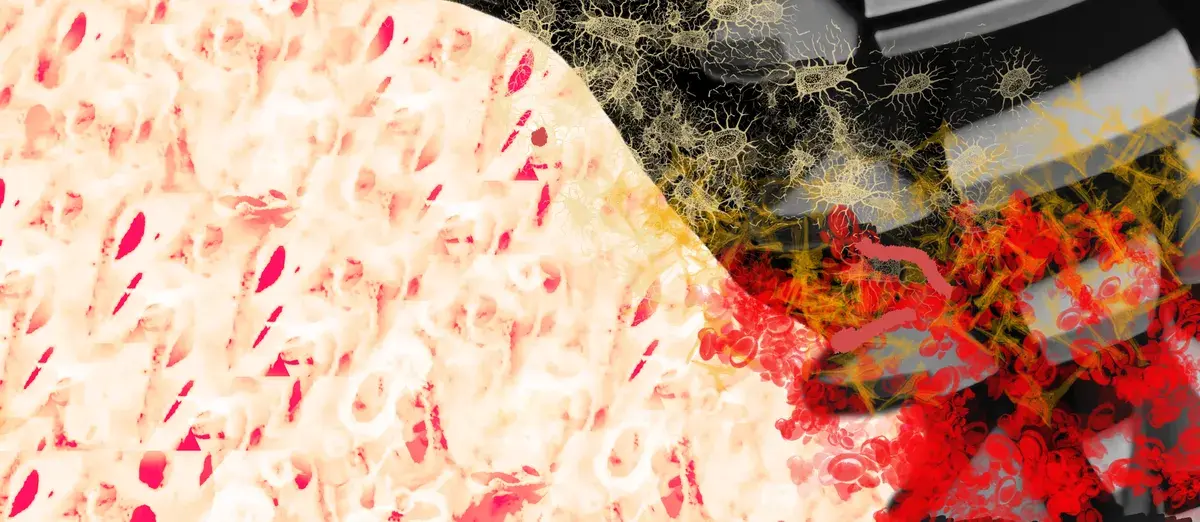

Esplora come il corpo reagisce all'impianto in titanio attraverso processi biologici complessi, che vanno ben oltre il semplice materiale del dispositivo.

macrofagi, osseointegrazione, impianti dentali, polarizzazione M1/M2, superfici implantari

Cosa sono i miofibroblasti e perché decidono se un impianto si osteointegra o fibrointegra. Superficie implantare, fattori di rischio e prevenzione.

Il processo di osseointegrazione coinvolge una sequenza di adsorbimento delle proteine e migrazione cellulare nei primi minuti, che precede la deposizio...